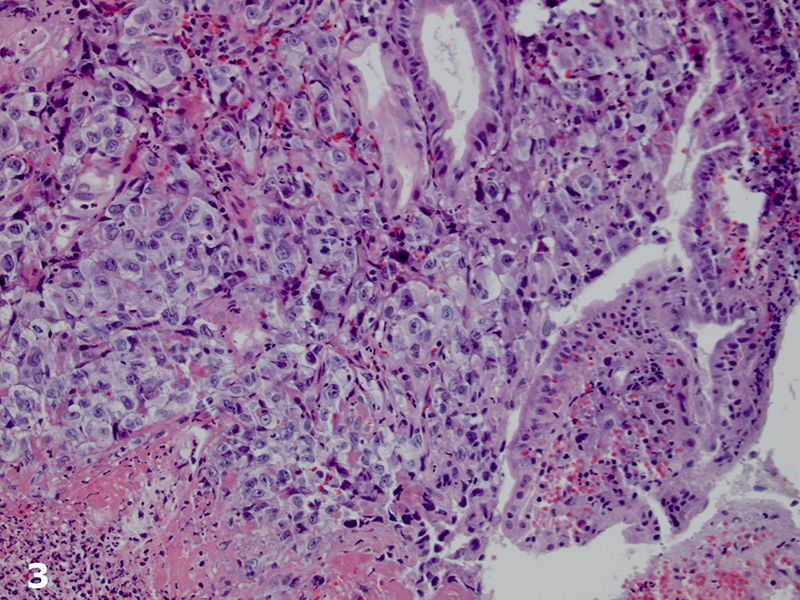

Imaging studies (computed tomography scan of the abdomen and chest radiograph) did not reveal a source for the bleeding or a mass lesion. The EGD demonstrated multiple red-brown polypoid masses within the stomach and duodenum (Figure 1).The biopsies, of both the stomach and duodenum, demonstrated large cells with amphophilic cytoplasm and irregular nuclei with vesicular chromatin and prominent nucleoli infiltrating the lamina propria (Figures 2 and 3). There was subtle vasoformation and, notably, no overlying dysplasia was identified. The neoplastic cells were positive for pan-cytokeratin, cytokeratin 7 (Figure 4), CD31 (Figure 5), and CD34. The neoplastic cells were negative for CDX2, TTF-1, S-100 protein, cytokeratin 20, cytokeratin 5/6, and calretinin.